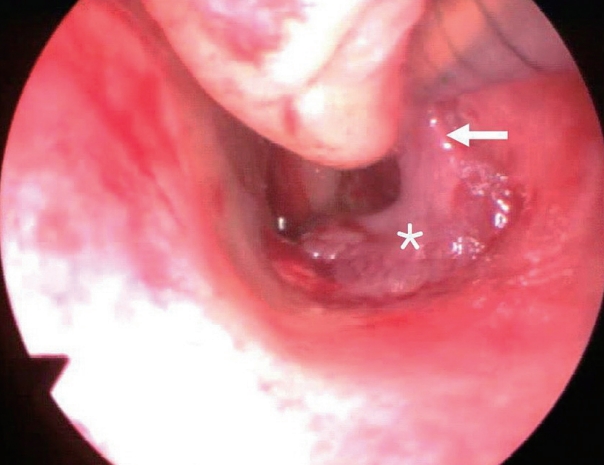

증 례65세 여자 환자가 2주 전부터 시작된 좌측 코막힘과 화농성 비루를 주소로 내원하였다. 고혈압으로 약물 치료 중이었으며 그 외 내과적 기저 질환은 없었다. 비내시경 검사에서 화농성 분비물을 동반한 경계가 불규칙적인 종물이 좌측 하비도의 후방을 채우며 후비공까지 진행되어 있었고, 종물 주변으로 하비갑개와 하비도 점막의 비후가 관찰되었다(Fig. 1).

Fig. 1.Preoperative endoscopic findings. A bizarre single polypoid mass (*) is located between the left inferior turbinate and the basal floor of the nasal cavity. S: septum, IT: inferior turbinate. Fig. 2. Preoperative CT findings. Axial (A) and coronal (B) view. CT shows soft tissue density at the basal floor of the nasal cavity. Bone erosion is not observed and paranasal sinus is clear. Fig. 3.Preoperative MRI findings. Axial (A) and coronal (B) view. An ovoid homogenous enhancing mass (arrowhead) appears to originate from the posterior inferior side of the left inferior turbinate (arrow) and extends to the choana. Fig. 4. Operative findings. A pedicle (arrow) of single polypoid mass (*) is attached to the posterior side of the inferior turbinate. REFERENCES1. Lopatin A, Bykova V, Piskunov G. Choanal polyps: One entity, one surgical approach? Rhinology 1997;35(2):79-83.